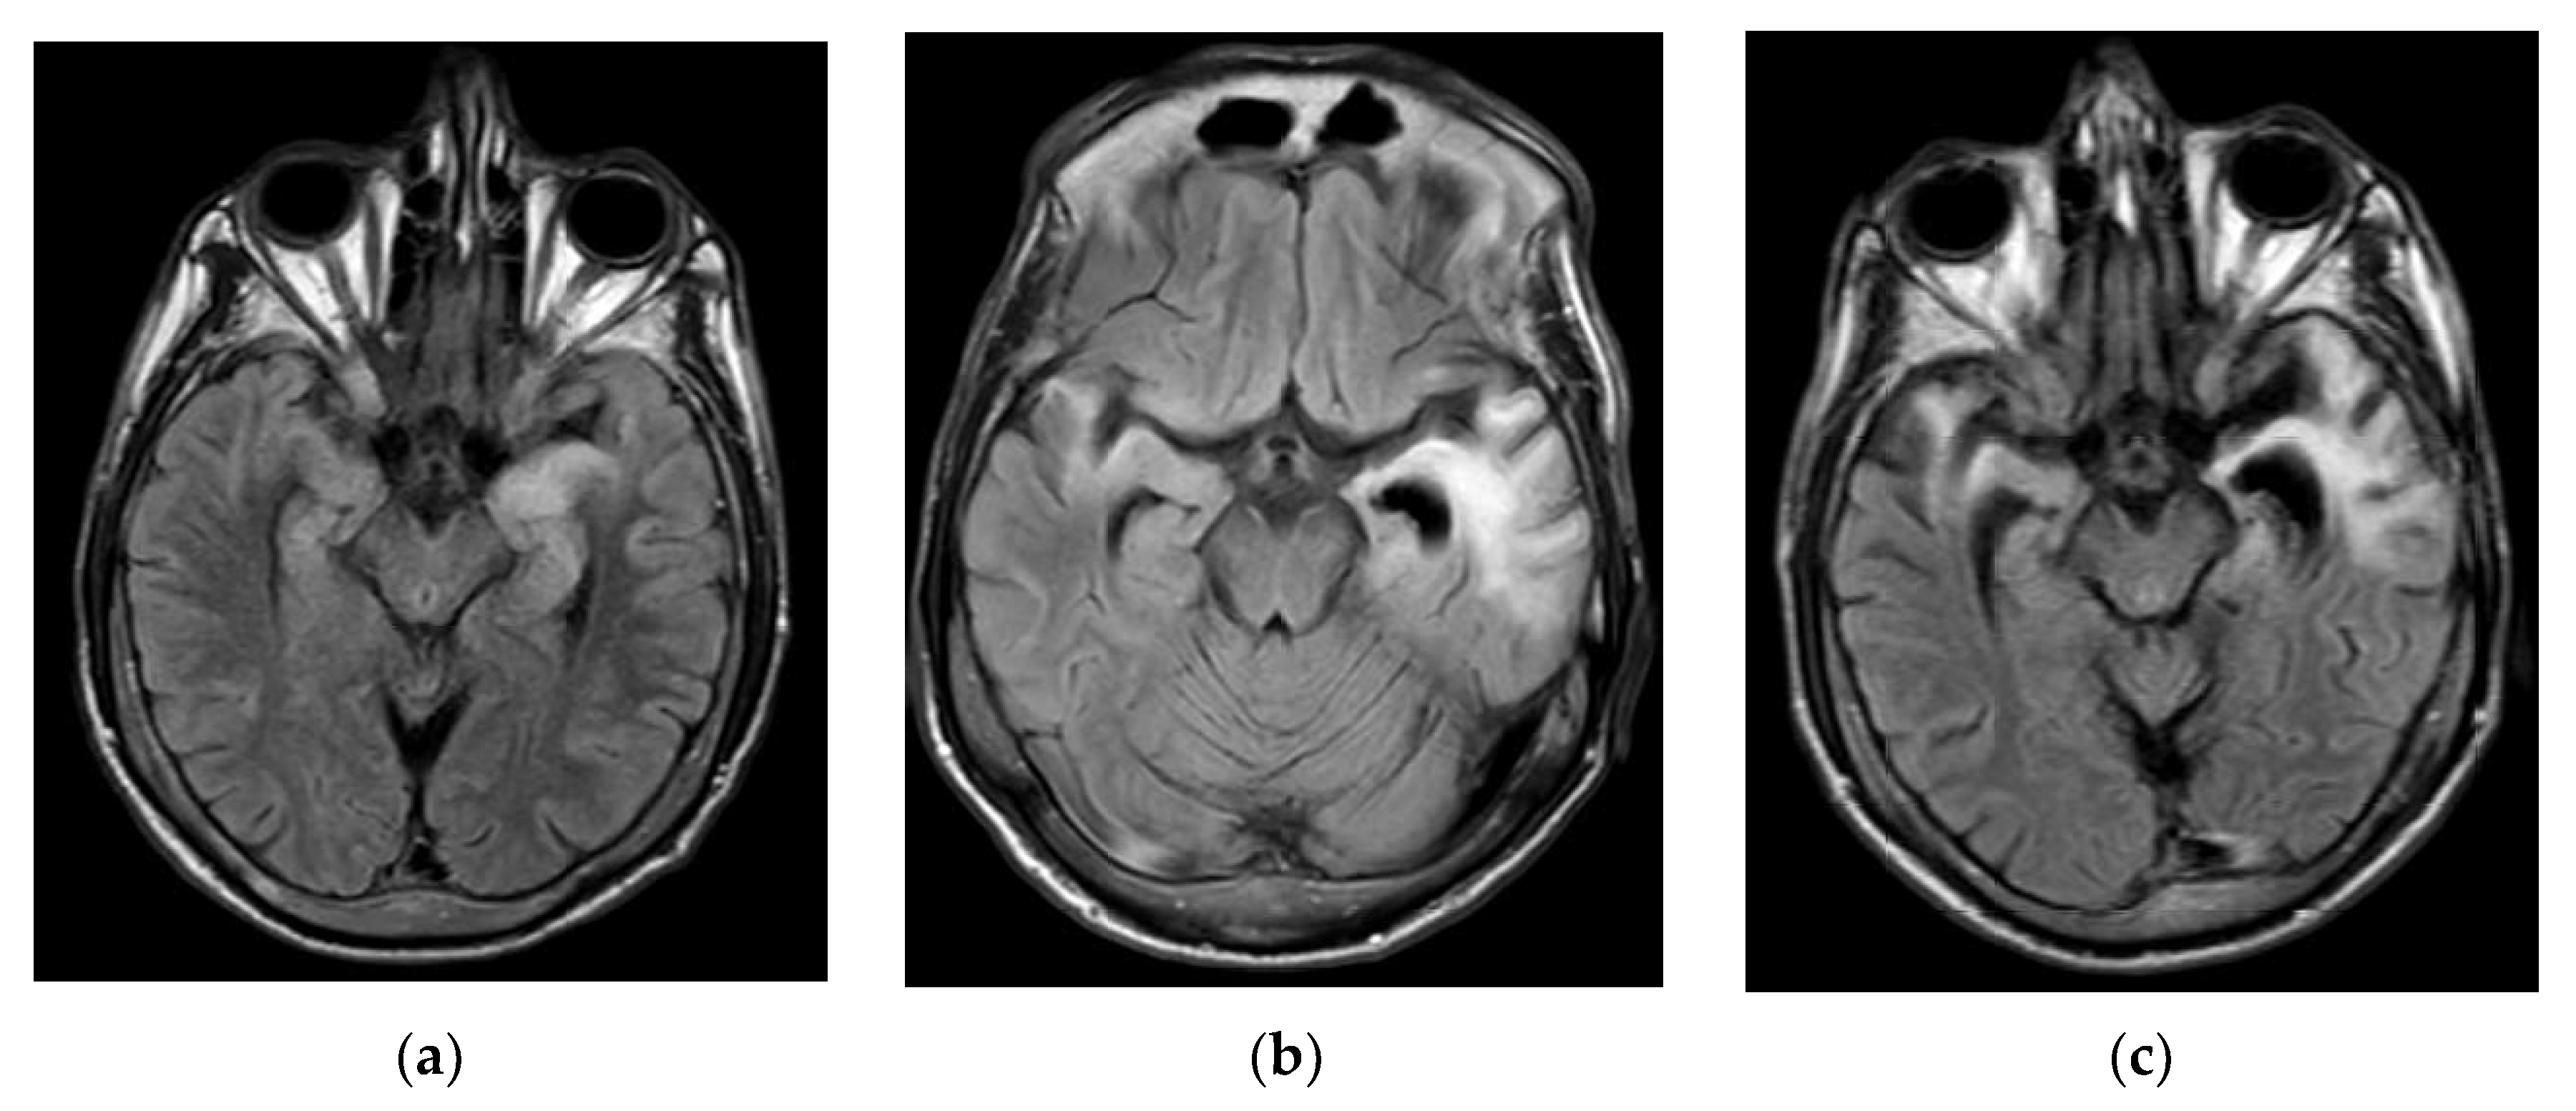

1.1. Admission 1

1.2. Admission 2

1.3. Admission 3